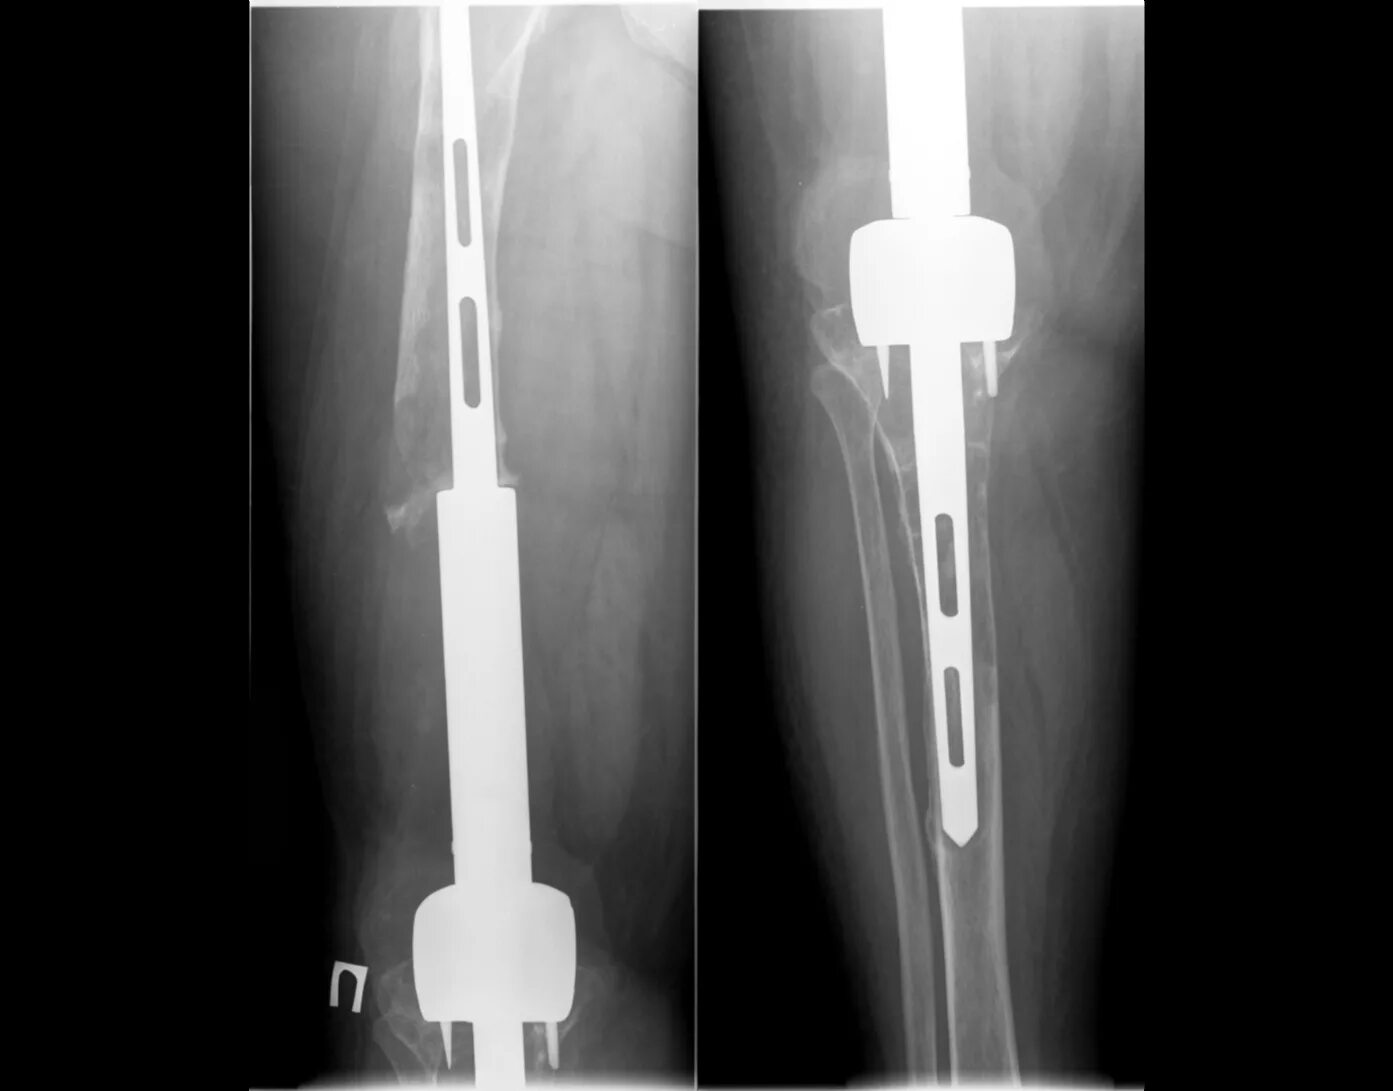

Остеосинтез мрт